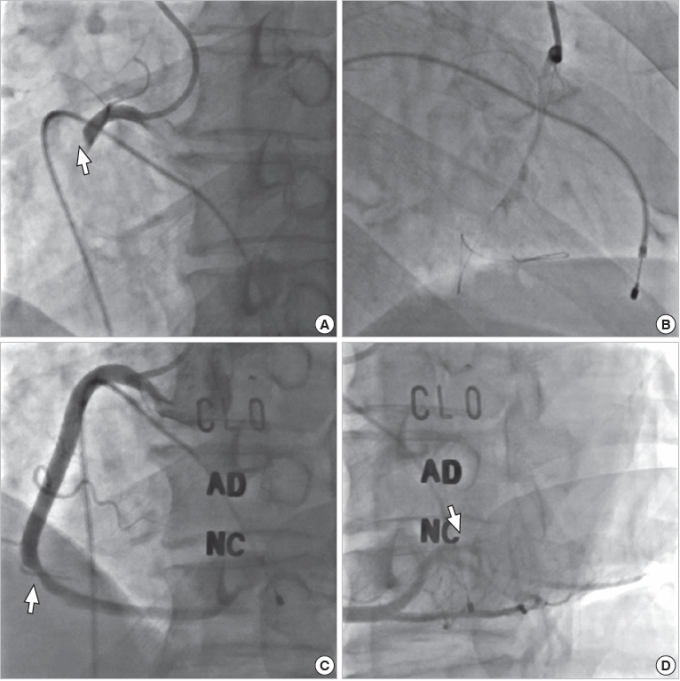

Qua hình ảnh chụp động mạch vành, bệnh nhân bị tắc hoàn toàn động mạch vành phải, do cục máu đông ở vị trí gần ngay lỗ vào (điểm xuất phát của động mạch vành phải). Kíp kỹ thuật đã can thiệp tiến hành nong và đặt stent thành công, tái lập dòng chảy động mạch vành. Sau khi can thiệp, bệnh nhân được chuyển về khoa hồi sức tích cực tiếp tục điều trị nội khoa. Đến nay, đã tỉnh táo hoàn toàn, sức khỏe ổn định, nhịp tim hồi phục trở lại, không cần sự trợ giúp của máy tạo nhịp nữa.

Kết quả của bệnh nhân trước và sau khi điều trị.